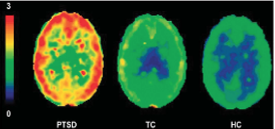

PTSD is an unmet clinical need.

Post-Traumatic Stress Disorder (PTSD) remains a significant unmet medical need, affecting millions worldwide with debilitating symptoms that impair daily functioning and quality of life. While existing treatments provide relief for some, many patients struggle with persistent anxious arousal—one of the most distressing and treatment-resistant symptoms of PTSD. The need for novel, evidence-based therapies that offer both efficacy and safety is more urgent than ever. Unlike emerging psychedelic-based treatments, which face challenges around safety, regulation, and broad patient acceptability, there is a clear demand for innovative therapies grounded in rigorous science and proven pharmacological mechanisms.

Neuritek Therapeutics is advancing a next-generation approach to PTSD treatment through the development of a first-in-class FAAH inhibitor—a promising drug candidate designed to reduce anxious arousal by modulating key GPCRs (G protein-coupled receptors) involved in stress regulation. This targeted mechanism has shown potential to address hyperarousal symptoms without the psychoactive side effects or regulatory hurdles of psychedelics. With a strong focus on safety, tolerability, and clinical validation, Neuritek aims to deliver a transformative treatment option that can meet the critical needs of patients who currently lack effective solutions.